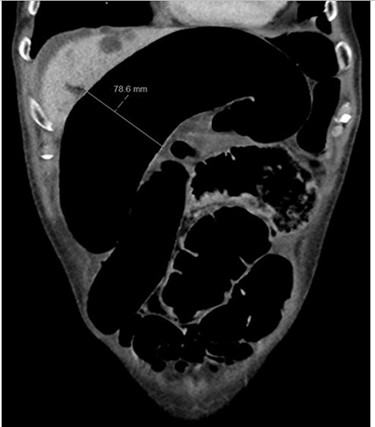

Blood tests on admission were unremarkable, with normal electrolytes levels and lactate. A plain abdominal film showed a typical appearance of caecal volvulus, with an inverted ‘comma sign’ (Fig. 4). A CT scan of the abdomen and pelvis with intravenous contrast was reported as sigmoid volvulus with the involved loops sitting predominantly in the right upper quadrant immediately inferior to the liver (Fig. 5).

Case two: a coronal slice of a CT scan of the abdomen and pelvis with intravenous contrast showing dilated large bowel loops; the radiology report suggested sigmoid volvulus with a centrally lying caecum.